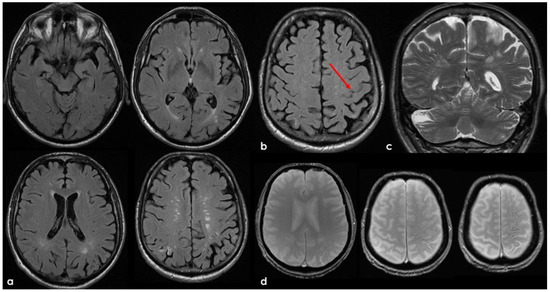

7. April 2018: Second Recurrent CAA-Related Inflammation

8. April 2018: Third Recurrent CAA-Related Inflammation